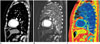

Virtual Non-Contrast or Unenhanced Imaging and Iodine Map

In all body regions, VNC imaging may replace a pre-contrast scan and substantially reduce radiation exposure, which is particularly useful in children. For example, Chen et al. (17) reported that split-bolus dual-energy CT urography allowed 56.4% reduction of radiation dose by eliminating the need for a pre-contrast scan. However, the size of calcification tends to be smaller on VNC imaging, as compared with that on true non-contrast imaging (14, 17, 18, 19, 20), and tiny calcifications or calcified stones may be overlooked on VNC imaging. On the contrary, incompletely removed iodine areas result in false positive findings (17). Usually, CT numbers of soft tissues are slightly overestimated on VNC imaging (14, 17, 18). The noise levels of the VNC images as well as iodine maps are strongly correlated with the inversion of the dual-energy ratio, emphasizing the importance of spectral separation (7, 21). Furthermore, greater spectral separation reduces the erroneous discrimination between iodine and calcium on VNC images.

In the abdominal region, VNC images allow better visualization of isodense cholesterol gallstones with accentuated contrast chiefly due to increased attenuation value of fat at higher tube voltage (20). Liver iron overload may be quantified by using an iron-specific three-material decomposition algorithm with similar diagnostic performance to MRI (22) and, therefore, it may be used as an alternative method when MRI is not available or contraindicated.

Similarly, synovial hemosiderin deposits can be identified on dual-energy CT in patients with pigmented villonodular synovitis (23). As in intravenously enhanced CT, VNC imaging may be applied to CT arthrography in the musculoskeletal region (23). In the musculoskeletal region, virtual non-calcium imaging may be used to evaluate the bone marrow that is beyond the scope of CT evaluation. Virtual non-calcium imaging subtracts calcium from cancellous bone and allows detection of acute traumatic bone marrow lesions including occult fractures and bone bruises, which cannot be clearly visualized on single-energy CT (23, 24, 25). Diagnostic performance of virtual non-calcium imaging tends to be better for small appendicular bones than axial skeletons. Adjustment of material decomposition ratio (r) is necessary for different tube voltage settings (1.45 for 80 and 140 kVp; 1.3 for 100 and 140 kVp) to eliminate bone mineral completely. Nevertheless, virtual non-calcium imaging is limited in evaluating bone marrow alterations close to the cortical bone or in sclerotic bone. In addition, false-positive results may occur due to the presence of normal red marrow, and other pathologies, such as osteonecrosis or degenerative changes, may mimic post-traumatic bone marrow lesions. A combined review of gray-scale images and color-coded images can facilitate the identification of small attenuation changes within the bone marrow (23, 24, 25). Of note, automatic color-coded bone marrow segmentation is incomplete, especially in the head region.